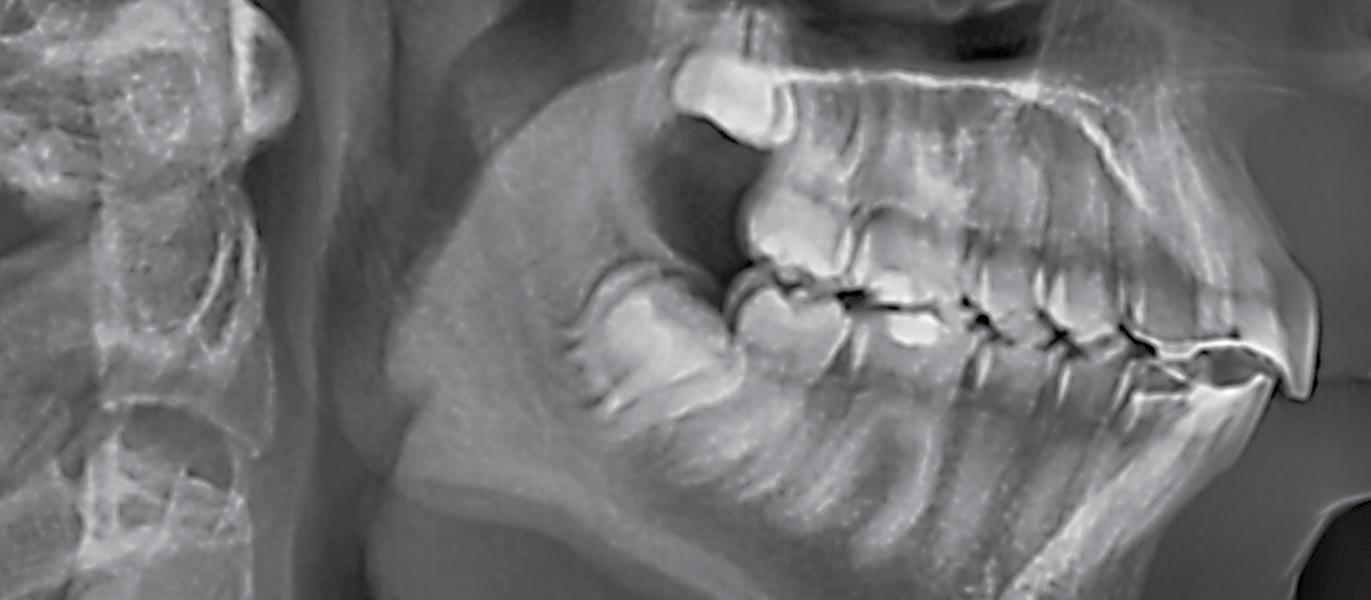

An orthopantomogram (OPG) revealed RL8 and LL8 were mesioangularly impacted and their roots were crossing both upper and lower white lines of the inferior alveolar canal (IAC). LL8 roots showed darkening of root at the level of IAC (Fig 1).

It was decided to request a Cone Beam CT to substantiate findings of the routine OPG in relation to the IAN.

CBCT revealed the following findings:

LL8: IAC was running buccal to roots of LL8 which had 3 roots (Fig 2).

RL8: IAC was seen running between the buccal root which was hooked mesially and lingual roots at its apex, vulnerable to surgical injury (Fig 3).